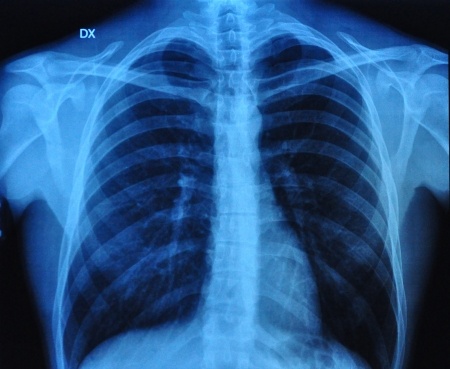

Obturacyjny bezdech senny stanowi niezależny czynnik ryzyka wystąpienia zatorowości płucnej. Do rozpoznawania nawrotu zatorowości płucnej wykorzystywana jest - między innymi - ocena stężenia D-dimerów w surowicy. Angela García Suquia i wsp. zaprojektowali badanie mające na celu ocenę z jaką częstością obserwuje się podwyższone wartości D-dimerów (>500 ng•mL−1) po zakończeniu leczenia przeciwkrzepliwego z powodu zatorowości płucnej wśród pacjentów z rozpoznanym obturacyjnym bezdechem sennym oraz u osób wolnych od tego schorzenia. Wyniki badania opublikowano na łamach czasopisma European Respiratory Journal.